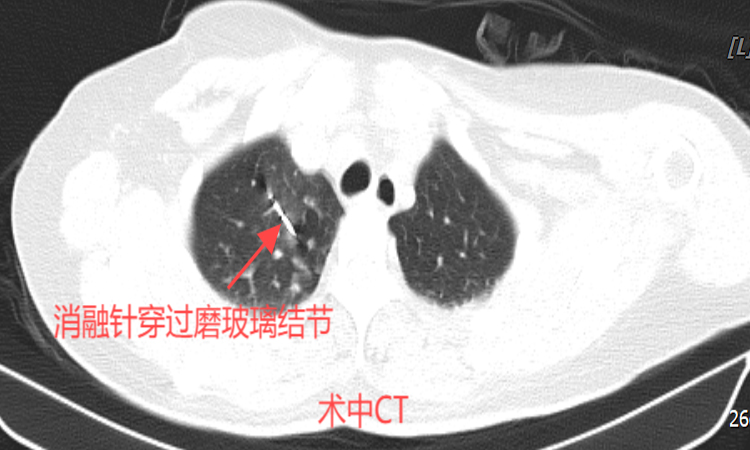

根据患者病情,微创介入科刘冰主任团队联合影像科进行了术前讨论和准备,制定了治疗方案。这是一种创新的微创治疗技术,在CT引导下,将直径仅2毫米的消融针精准插入肺结节内部,利用微波产生的高温破坏病变组织,使结节的细胞变性坏死,从而达到治疗目的。

在征得患者及家属同意后,刘冰主任带领团队进行了肺部多发结节微波消融术。术中,选取患者合适体位,CT确认进针通道,然后在CT引导下精准置入微波消融针至结节处进行消融。40分钟后,手术顺利完成,复查胸部CT显示:消融治疗范围覆盖目标病灶,无气胸及出血。术后患者没有特殊不适,安全返回病房。